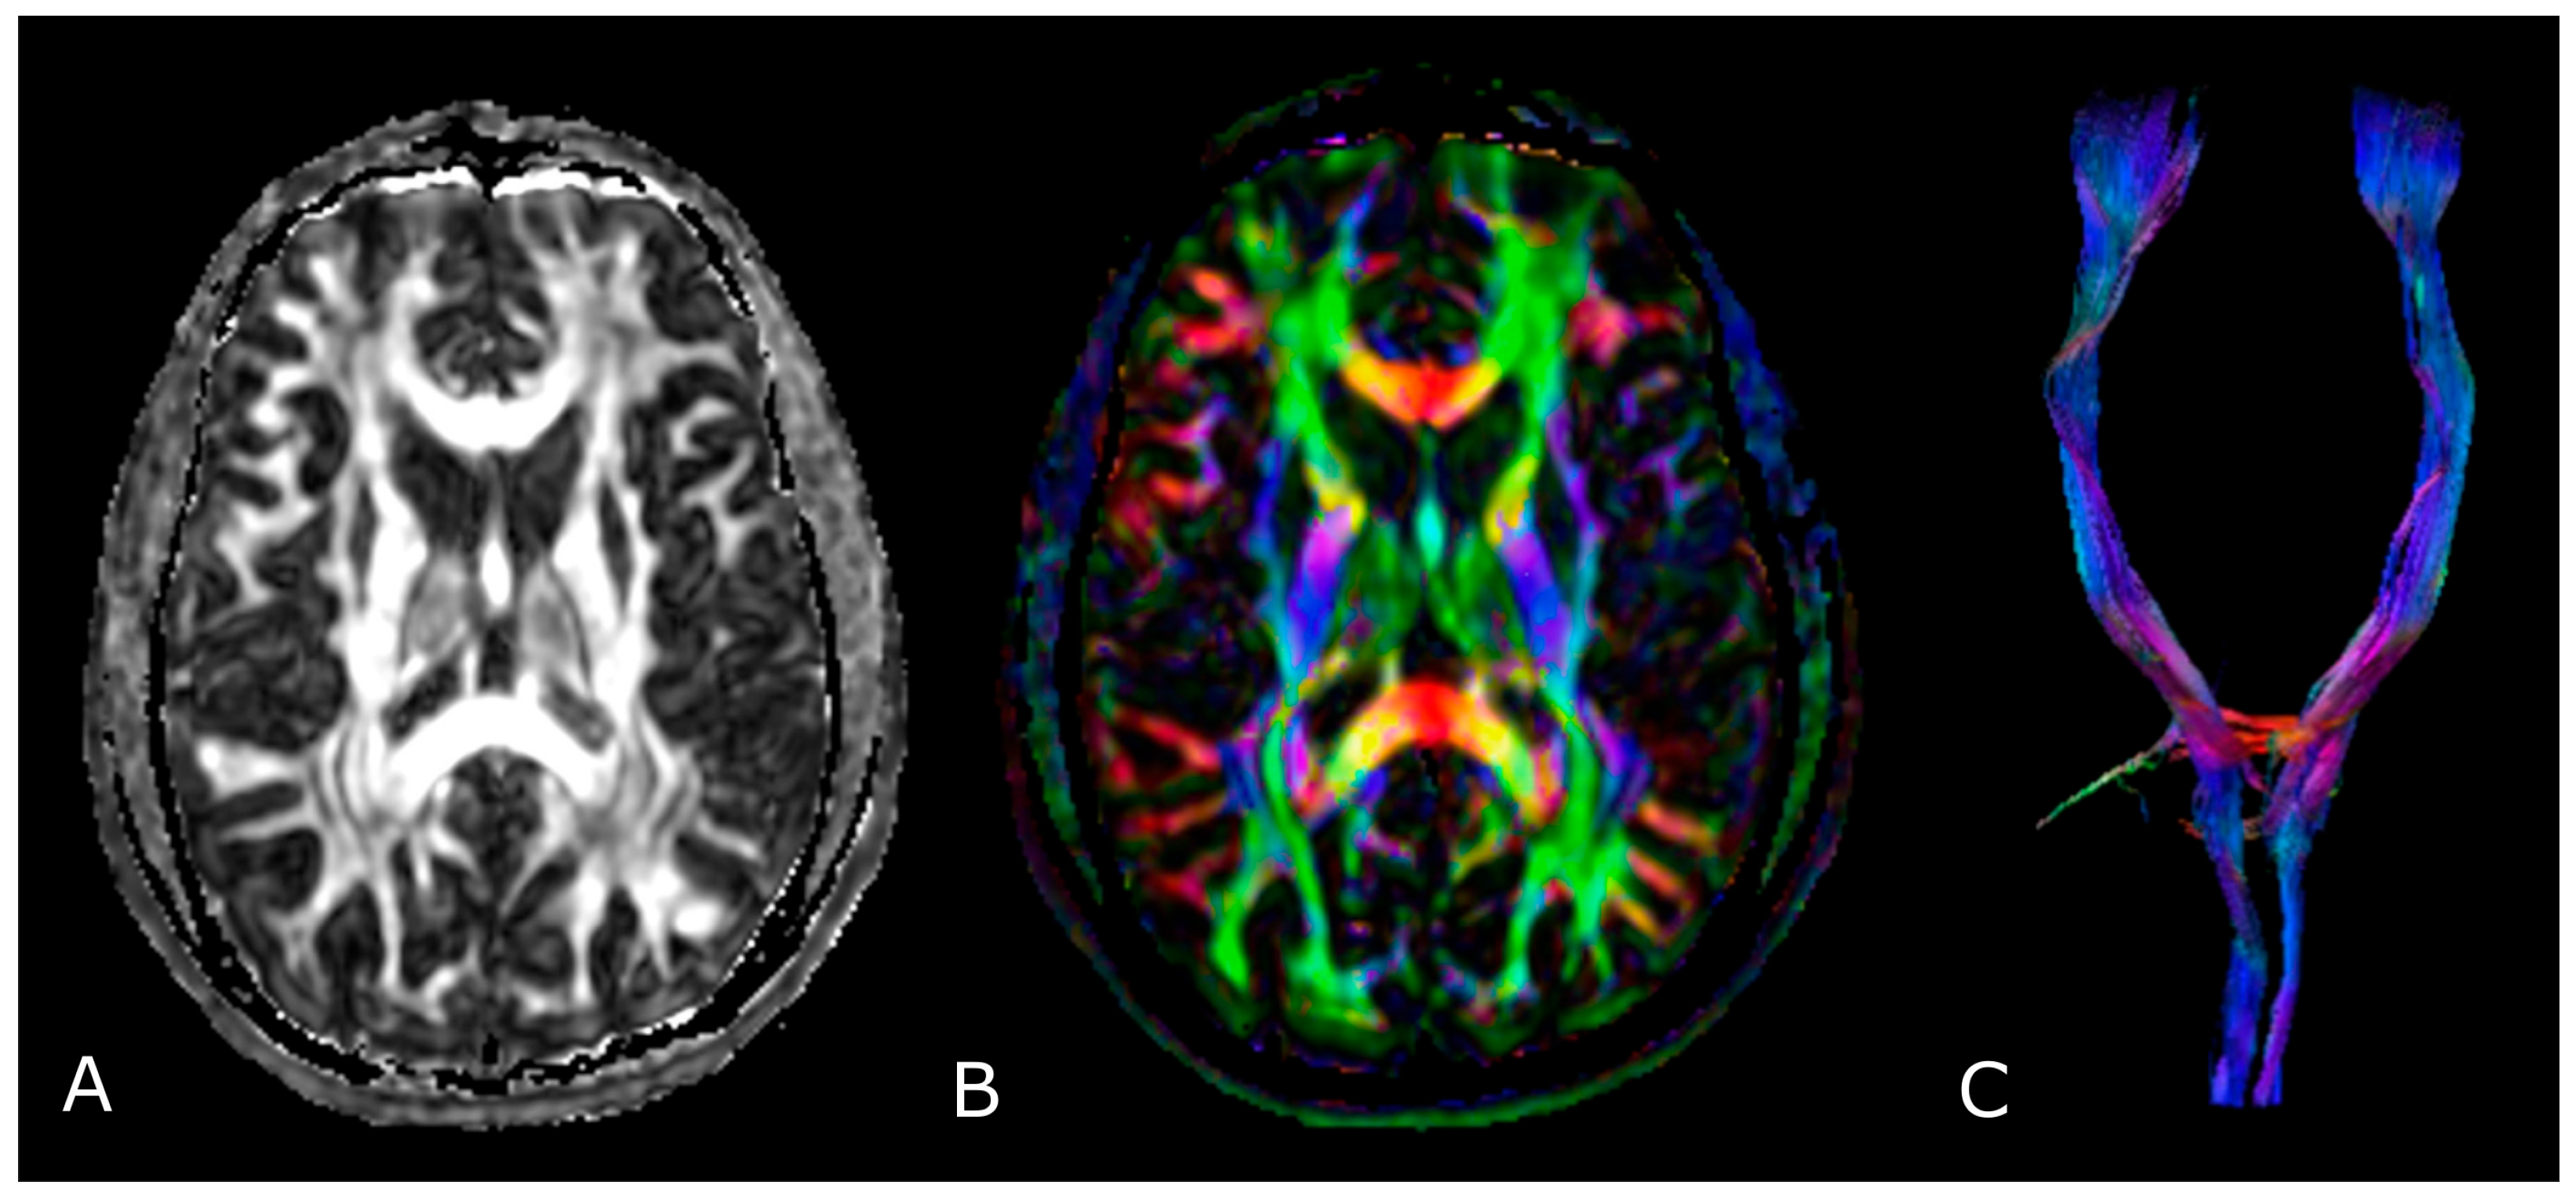

The most used indices in DTI are the mean diffusivity (MD), which corresponds to the magnitude of diffusion, and fractional anisotropy (FA), which scales from 0 (completely isotropic) to 1 (completely anisotropic) [60]. DTI images are commonly displayed as color encoded FA maps, with standardized colors for the different fiber orientations: red (left-right), green (antero-posterior), and blue (cranio-caudal) (Figure 6B,C) [60]. With the use of specific software and through the definition of a seed region of interest (ROI), fiber tractography enables 3D visualization of fiber bundles, thus allowing in vivo projection of brain WMTs (Figure 6C).

Figure 6.

Diffusion Tensor Imaging: (A) normal FA map without any directional information; (B) Combined FA and directional map. Colors indicate directions as follows: red, left-right; green, anteroposterior; blue, superior-inferior. Brightness is proportional to FA; and (C) 3D visualization of normal corticospinal tracts.